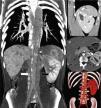

The patient was referred for further investigation by MDCT angiography, which revealed prominent kinking of the aortic arch distal to the origin of the innominate artery and fusiform dilatation of the descending aorta (but with no significant collateral circulation), consistent with the echocardiographic findings of aortic pseudocoarctation (Figure 1a). The prominent blood vessel anteriorly crossing the descending aorta shown on the TTE was identified as a dilated hemiazygos vein (Figure 1b). Bilateral morphological left bronchi were also noted (Figure 1c). A systemic venous drainage anomaly affecting the inferior vena cava (IVC) was suspected and abdominal MDCT imaging was performed. This showed a duplicated IVC with left dominance. The left IVC was formed by the junction of the left internal and external iliac veins and continued cranially through the hemiazygous system without joining the right IVC. The latter was formed by the junction of the left internal and external iliac veins and continued cranially up to the liver, draining into the right suprahepatic vein (Figure 2a). Before continuing as the IVC on both sides, the common iliac veins were interconnected by transverse venous anastomoses and on the left side two renal veins were found draining into the left IVC. An extensively septated left spleen was also present (Figure 2b). Moreover, agenesis of the pancreatic tail and lateral part of the body were also noted, as well as right renal agenesis and left hydronephrosis and hydroureter (Figure 2c and 2d).

(a) Three-dimensional volume rendering of the thoracic aorta. The ascending aorta is normal, but there is significant tortuosity of the aortic arch and fusiform dilatation of the descending aorta; (b) coronal plane volume rendering reconstruction showing a dilated hemiazygos vein (black arrows) anteriorly crossing the descending aorta; (c) coronal plane volume rendering reconstruction demonstrating the presence of bilateral left bronchi (hyparterial bronchial position). Ao: aorta; LP: left pulmonary artery; RP: right pulmonary artery.

(a) Coronal plane volume rendering reconstruction showing duplicated IVC with left dominance, with the left IVC (black arrow) continuing cranially through the hemiazygos system without joining the right IVC and the right IVC (white arrow) continuing to the liver; (b) sagittal reformatted contrast-enhanced computed tomography showing an extensively septated spleen consistent with polysplenia (arrows); (c) axial reformatted contrast-enhanced computed tomography showing associated absence of the pancreatic tail and lateral part of the body (arrow); (d) coronal three-dimensional volume rendering showing absence of the right kidney. Ao: aorta.